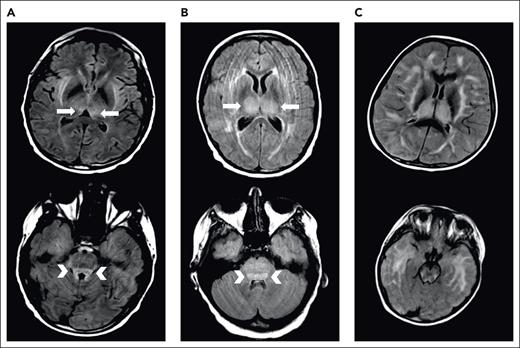

We typically administer thiamine repletion in the setting of severe CRS or ICANS. During severe ICANS, MRI changes resembling those in Wernicke encephalopathy, with T2/FLAIR hyperintensities in the dorsomedial thalami and tectal plate, have been reported12 (Figure 1). We have found abnormally low thiamine levels in hospitalized patients requiring CAR T-cell therapy. Inflammation is thought to be a factor driving thiamine-deficient state, and patients with sepsis are frequently thiamine deficient.50 Thiamine deficiency decreases BBB competence.51 We supplement patients experiencing severe CRS or ICANS with high-dose thiamine for 3 days, followed by daily thiamine until CRS and ICANS resolve.

Examples of MRI changes during severe ICANS. Brain MRI during severe ICANS may rarely demonstrate symmetric T2/FLAIR hyperintensities in dorsal medial thalami (top; arrows) and tectal plate (bottom; arrowheads) resembling imaging changes associated with Wernicke encephalopathy. (A) MRI images from an adult patient with grade 4 ICANS. (B) MRI images from a pediatric patient with grade 4 ICANS. (C) Images from a pediatric patient with diffuse cerebral edema.